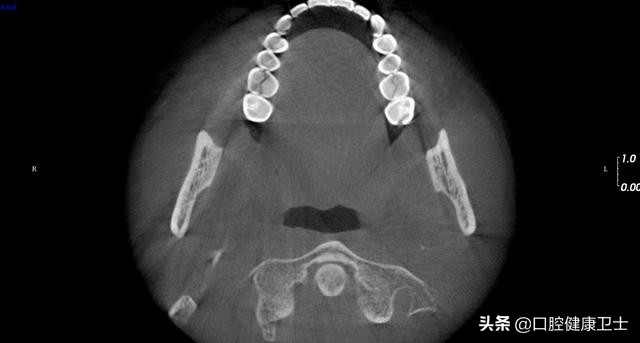

CT见,右上第一磨牙近远中向劈裂,左上第一磨牙也是近远中向劈裂,暂不处理。

CT见,右上第一磨牙劈裂至髓室,左上第一磨牙同样,暂不处理。